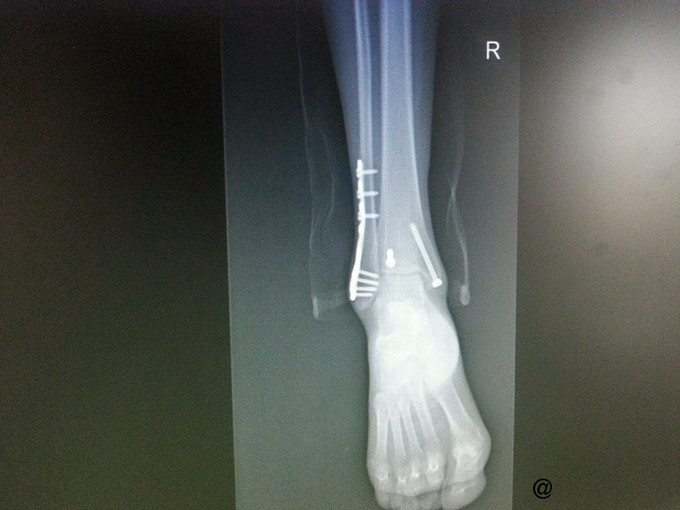

主诉:右三踝骨折ORIF术后一年半,要求取出内固定 病史:患者一年半前因外伤致右三踝骨折,1年前我院行“右三踝骨折ORIF术”。术顺,目前患者术后恢复良好,无切口处疼痛红肿热痛、无畸形愈合,为取出内固定再次入院。

查体:右侧外踝处可见一纵行8cm左右的陈旧性手术疤痕,愈合良好,踝关节无压痛,无肿胀,活动可。四肢肌力、肌张力正常。足趾自主活动良好,末梢血运正常,足背动脉搏动可及,皮肤感觉存在。其他肢体未见明显异常。 辅查:右侧踝关节正侧位片:右侧内外踝骨折内固定术后,内固定器在位,断端对位对线可。

诊断:取除骨折内固定装置(右三踝骨折术后) 处理:右踝关节骨折术后取内固定术